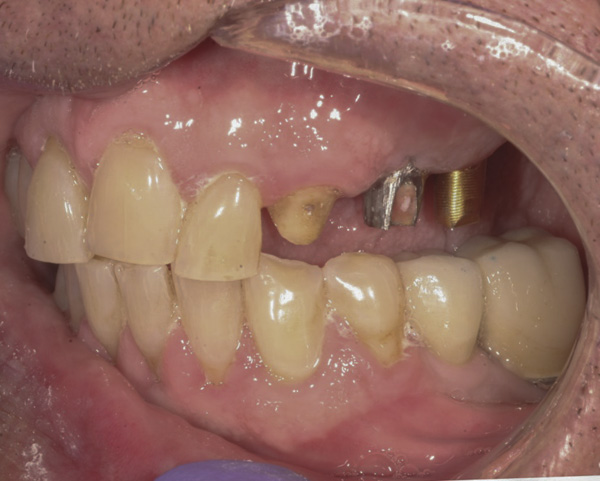

Background: The patient in this case presented with a failing dentition due to generalized severe periodontal disease with secondary endodontic lesions. She adamantly refused to wear removable transitional prostheses. Full maxillary and mandibular extractions were performed in the first phase of treatment. Not all implants could be placed in this initial phase due to the need for healing of certain grafted sites. The implants placed in this first phase were loaded with conical abutments and, in some cases, their angulated counterparts (Figure 16 and Figure 17). These stock titanium abutments were selected to avoid the need, as in Case 3, to change or remill the more costly custom abutments. They also have the advantage of making it unnecessary to use temporary cement near and around surgical sites, as they use occlusal screws only for retention.

Results: Stock titanium abutments were used until all tissue healing was achieved and the secondary implants had healed. Figure 18 shows the maxillary and mandibular custom abutments inserted. Figure 19 shows a close-up of the patient’s right side quadrants, depicting the final case 15 months after initial treatment began. Recession can be seen around units corresponding to tooth Nos. 5 and 6. In this case, the authors attempted to minimize recession susceptibility by employing stock temporary screw-retained abutments during healing phases throughout the initial stages of the treatment plan. Despite these efforts, recession still occurred in certain areas where the implants were labially placed. Since the photographs shown in this case were taken, an unsuccessful attempt was made by the patient’s surgeon to graft soft tissue around these sites with recession.

Quantity of buccal bone—Le and Borzabadi-Farahani concluded that a minimum of 2 mm of facial bone is necessary to prevent future recession.23 Bashutski and Wang noted that the most common esthetic complication is gingival recession, and cited inadequate buccal bone thickness, implants placed too far buccally, and failure to graft “jumping distance” during immediate placement in the etiology of recession.22 Case 5’s final result (Figure 19) shows more than 2 mm of labial recession around the implant-supported abutments at site Nos. 5 and 6 (this was also the case at site Nos. 13 and 14). Referring back to Figure 17, it is apparent that site Nos. 5, 6, 8, and 12 demonstrate very little buccal soft tissue due to the labial placement of the implants. Butler and Kinzer support the premise that there must be adequate bone volume facially, even when the implant is placed ideally, and they found that many complications are related more to the implant position and the associated anatomical findings.21

Buccal-labial position of implants—Saadoun and Touati concluded that the buccal orientation of the implant will impinge upon the buccal cortical wall and induce bone resorption and apical migration of the tissue.13 Chu et al reported that if the implant is not placed more palatally and 3-mm to 4-mm apical to the free gingival margin to assure the proper emergence profile, the esthetic outcome may be compromised.34 Bengazi et al’s 2-year longitudinal study demonstrated that anteriorly positioned implants demonstrated slightly more recession than implants in posterior positions.17 Buccal implant placement can be clearly seen in Case 5 (Figure 17) with healing abutments in place.

Proximity to adjacent implants—Tarnow et al24 and Tarnow et al25 recommend that a minimum of 3 mm of bone exist between two adjacent implants. In site Nos. 13 and 14 (Case 5) the fixture heads have less than 2 mm between them, and the abutments have less than 1 mm (Figure 17). Because interdental tissues do not have the same level of support between implants as they do with natural teeth, interdental distance becomes more critical in predicting the final soft-tissue position.

Figure 16 First-phase implants loaded with conical abutments and, in some cases, their angulated counterparts.

Figure 16

Figure 17 First-phase implants loaded with conical abutments and, in some cases, their angulated counterparts.

Figure 17